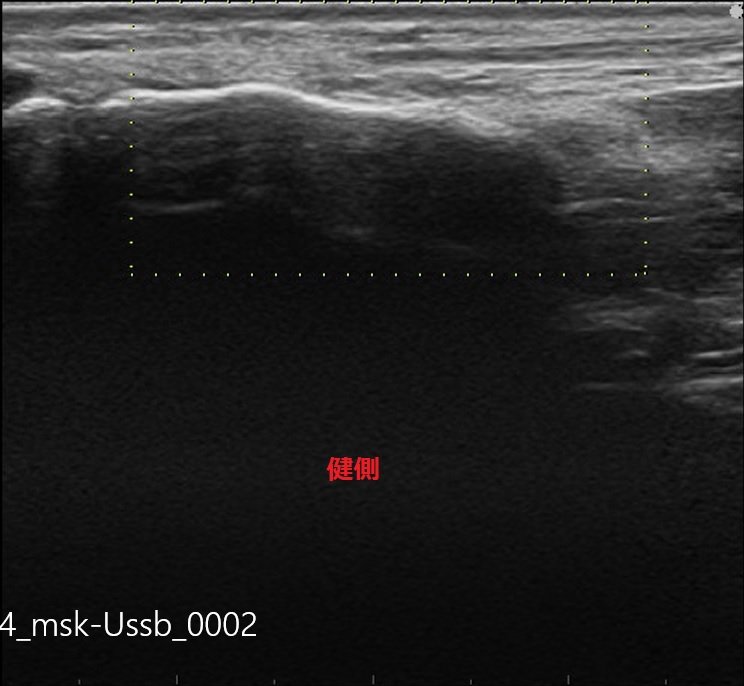

今回はエコー検査を行い、まだ疲労骨折にはいたっていないですが、

このまま無理に動いていると、必ず疲労骨折を発症する為、安静・治療となりました。

中足骨骨膜炎-健側.jpg